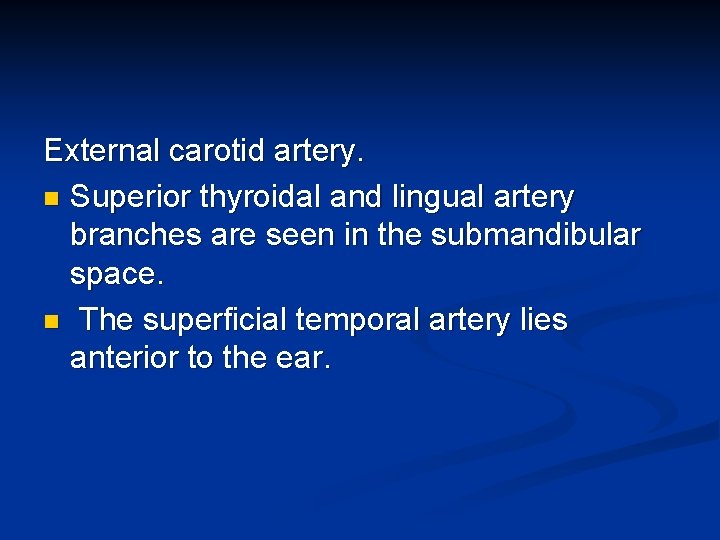

External Carotid Artery

External carotid artery. n Superior thyroidal and lingual artery branches are seen in the submandibular space. n The superficial temporal artery lies anterior to the ear.